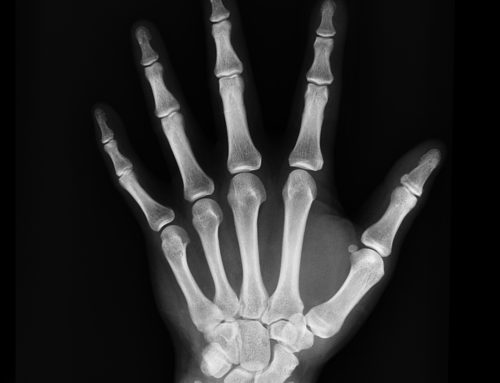

When you think of bone, usually the first thing you think of is calcium, and rightfully so. Calcium is the most abundant mineral in the human body and our bones store more than 99% of it. But we can’t forget that bone tissue also stores other essential minerals too.

The body is constantly creating new bone tissue and breaking down old bone tissue in a process called bone remodeling. In order to build new bone, new tissue formation must exceed breakdown of old tissue. Calcium and other minerals are deposited when new tissue is created.

However, when levels of calcium in our blood are low, our body goes to the calcium stores in our bone so that it can continue to regulate heart rate, contract muscles and regulate nerve impulses. As we get older, we tend to lose bone tissue faster than we can create it.

The inability to create new bone can leave us susceptible to osteoporosis, osteopenia and other bone conditions. There are many things related to diet and lifestyle that can impact bone health. You can read about six of them below.